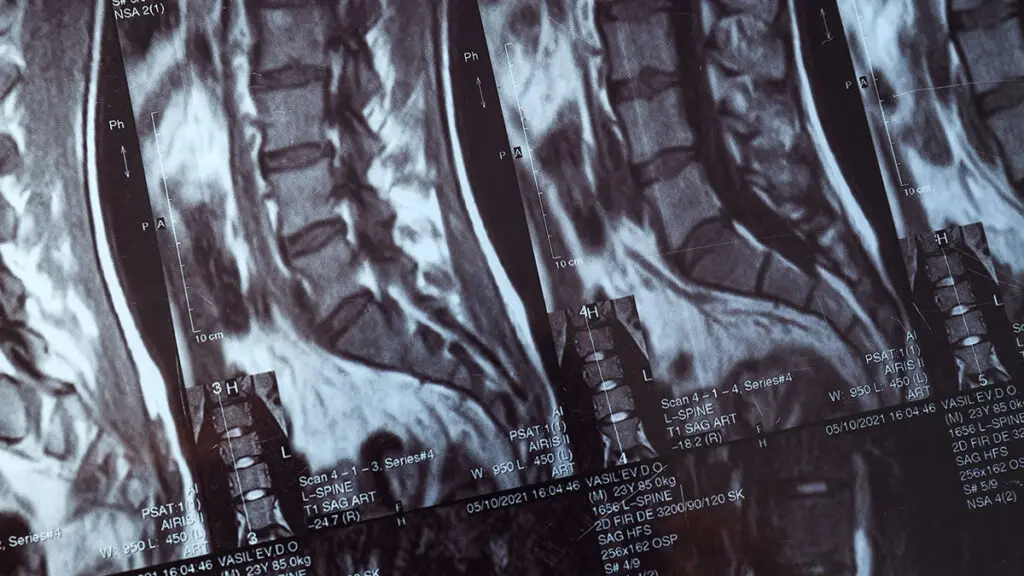

Global Spine Solutions è il centro di neurochirurgia vertebrale di eccellenza a Roma per chirurgia colonna vertebrale. I nostri neurochirurghi eseguono interventi con tecniche mininvasive all'avanguardia, che consentono di minimizzare il trauma chirurgico, ridurre i tempi di degenza e accelerare il recupero funzionale del paziente rispetto alla chirurgia tradizionale.

Ogni procedura di chirurgia colonna vertebrale viene pianificata in modo personalizzato, dopo un'attenta valutazione clinica e strumentale. Il team multidisciplinare di Global Spine Solutions discute ogni caso in collegialità per garantire il miglior risultato possibile, assicurando al paziente un percorso di cura trasparente dalla diagnosi fino alla riabilitazione post-operatoria.